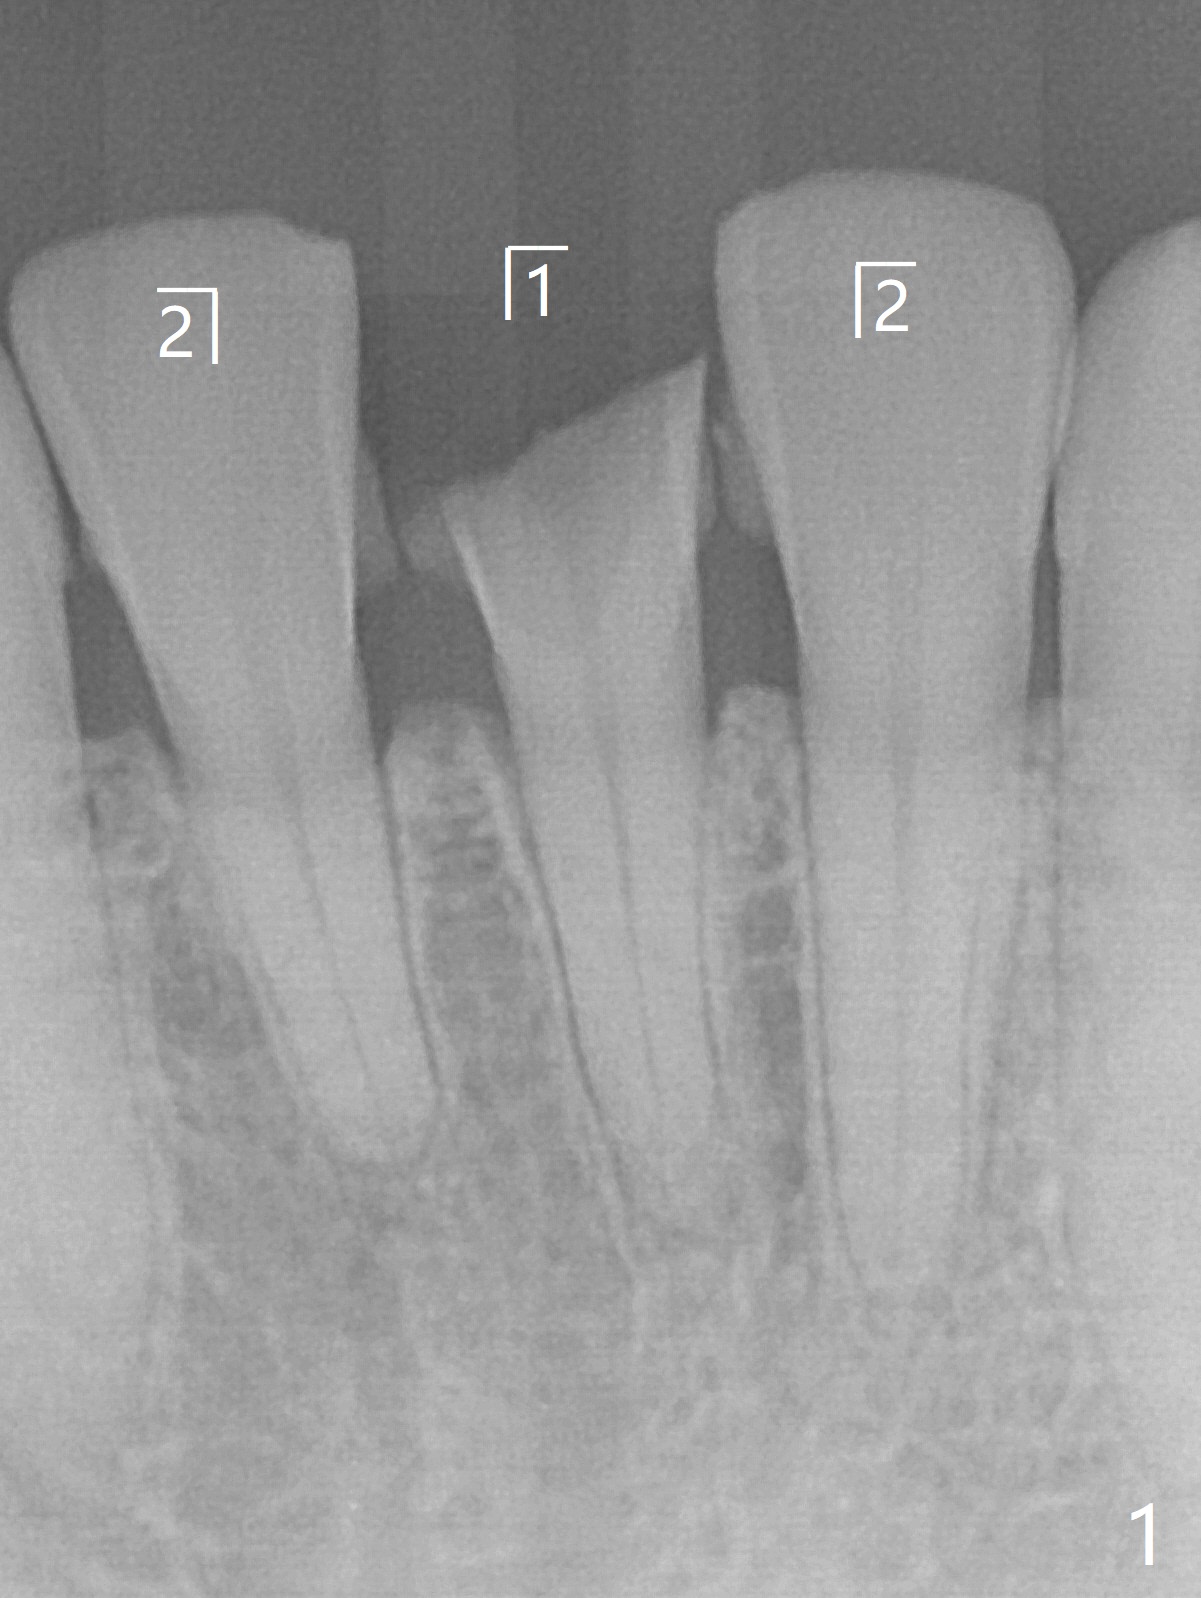

A 31-year-old woman fractured the lower left central incisor when it was hit by her 2-year-old son's head with mesiobuccal subgingival margin (Fig.1). After RCT (Fig.2), gingivectomy is conducted with eletrosurg to expose the fractured margin (Fig.3). In 2 days, a prefabricated fiber post will be bonded with the tooth and the fractured fragment together. To extend the use of the incisor, two implants are required (Fig.4). As scheduled, the patient returns with the fractured portion (Fig.5,6 (buccal (B) and lingual (L) views)). The periodontal dressing is in place (Fig.7 P). After preparation of the post space, the fiber post (Fig.10 (P)) is bonded with resin cement (Fig. 10 ^ and *) to the tooth and fragment with rubber dam (Fig.8). The patient is pleased post occlusal adjustment (Fig.9).